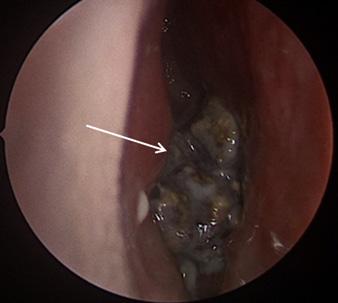

The patient was admitted to the medical intensive care unit (MICU) where he remained intubated for several days. An echocardiogram was performed, which was overall unremarkable, including no sign of mitral valve disease or depressed left ventricular ejection fraction. A bronchoscopy was performed, which showed no signs of inhalation injury, and serial aliquots showed successive clearing, inconsistent with diffuse alveolar hemorrhage. A bronchoscopic culture was obtained that grew methicillin-sensitive Staphylococcus aureus (MSSA). The patient’s blood cultures had been negative up to that point; so his antibiotic regimen was narrowed to cefazolin to cover MSSA pneumonia. Despite continued treatment, the patient’s clinical condition and ventilator requirements did not improve.

Point-of-care bronchoscopy is the only other major diagnostic tool to consider in the evaluation of massive hemoptysis. Availability, however, is inconsistent, and its diagnostic yield is generally lower than that of CT. It would not seem to have much value in this patient, although it could have been considered had the patient been too unstable for transport to a CT scanner.